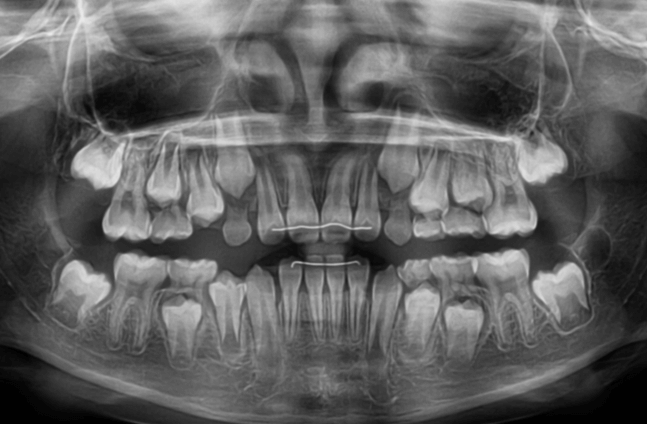

早期矯正治療 叢生症例② 翼状捻転

主訴 | 歯並びの乱れを気にされて来院された患者様です。将来的なスペース不足と歯のねじれ(翼状捻転)が懸念されました。 |

---|---|

診断結果 | 8歳9か月の女児。 歯列全体に叢生(乱れ)が認められました。翼状捻転による咬合不調も確認されています。 |

治療内容 |

|

治療後の経過 | 動的治療は2年10か月で終了後も3〜4か月ごとに定期検診を実施し、上下顎骨の成長発育が落ち着いてから本格矯正治療を行います。 |

治療期間 | 動的治療期間:2年10か月 通院回数:19回 |

治療費用 | 430,000円(税別) |